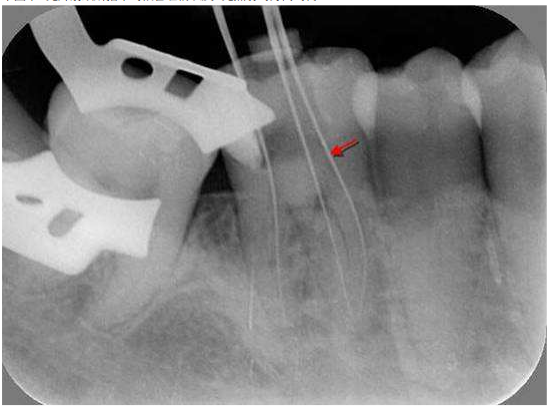

10.下圖中X光片箭頭所指示的根管名稱以及X光照射的方向為何?

(A)近心頰側根管,X光從遠心側往近心側照 (B)近心頰側根管,X光從近心側往遠心側照 (C)近心舌側根管,X光從遠心側往近心側照 (D)近心舌側根管,X光從近心側往遠心側照